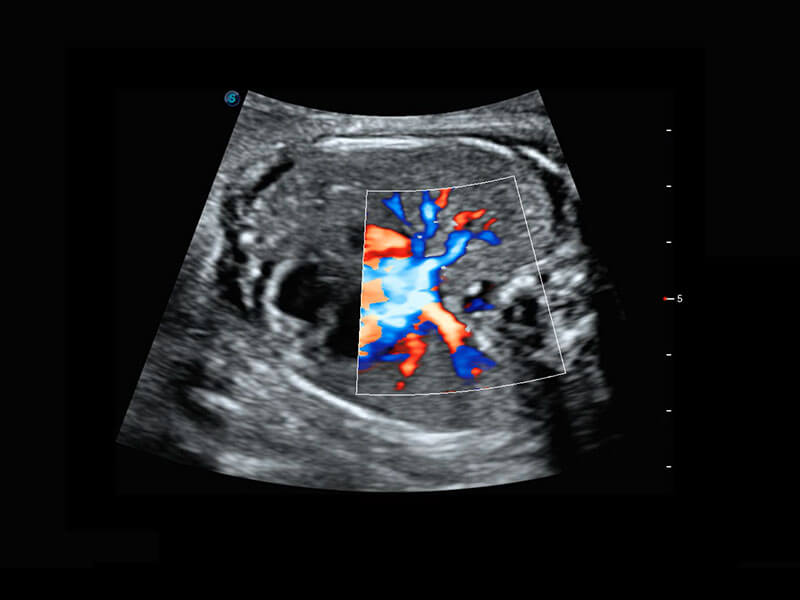

胎儿体循环

四腔心血流